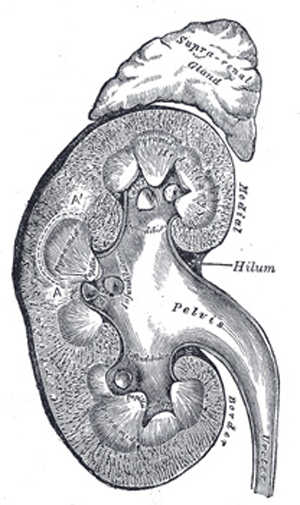

Joseph Murray和David Hume在波士顿的Peter Bent Brigham Hospital施行了第一例成功的人类肾脏移植手术。尽管当时没有抗排斥药物,但幸运的是,接受肾移植的小伙子的供肾来自于同卵双生的双胞胎兄弟,他幸运的再活了8年。